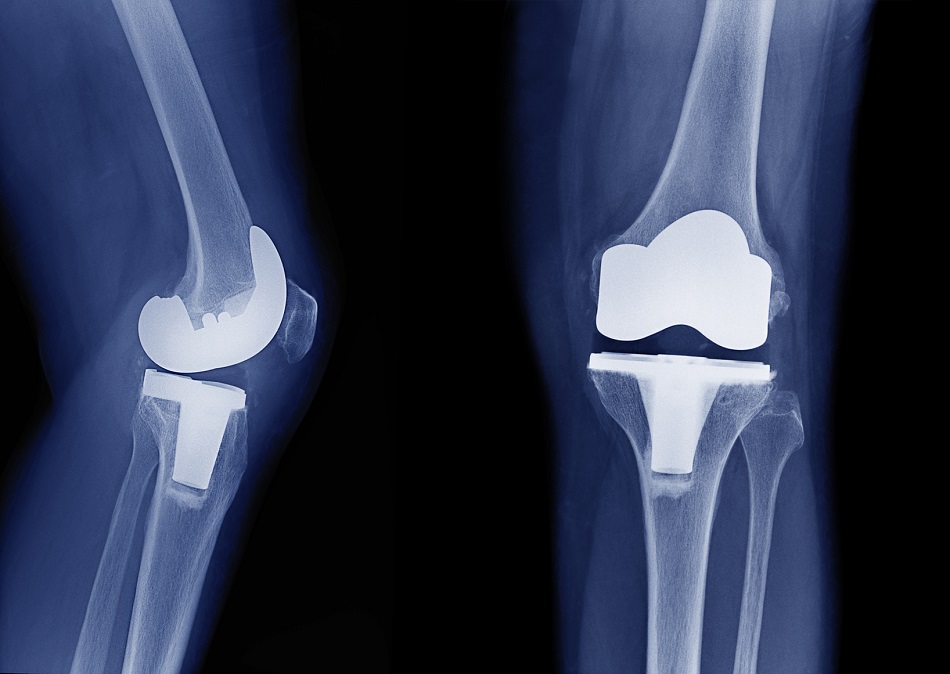

Discrepancia de miembros inferiores en artroplastia total de rodilla. ¿Es realmente un problema?

La incidencia de discrepancia de longitud de miembro inferior tras el con reemplazo total de rodilla fue del 30%. No se requirió  intervención como consecuencia de dicha discrepancia. Los resultados funcionales y dolor al seguimiento alejado no demostraron diferencias entre ambos grupos. Rev Fac Cien Med Univ Nac Cordoba , 16 de septiembre de 2022